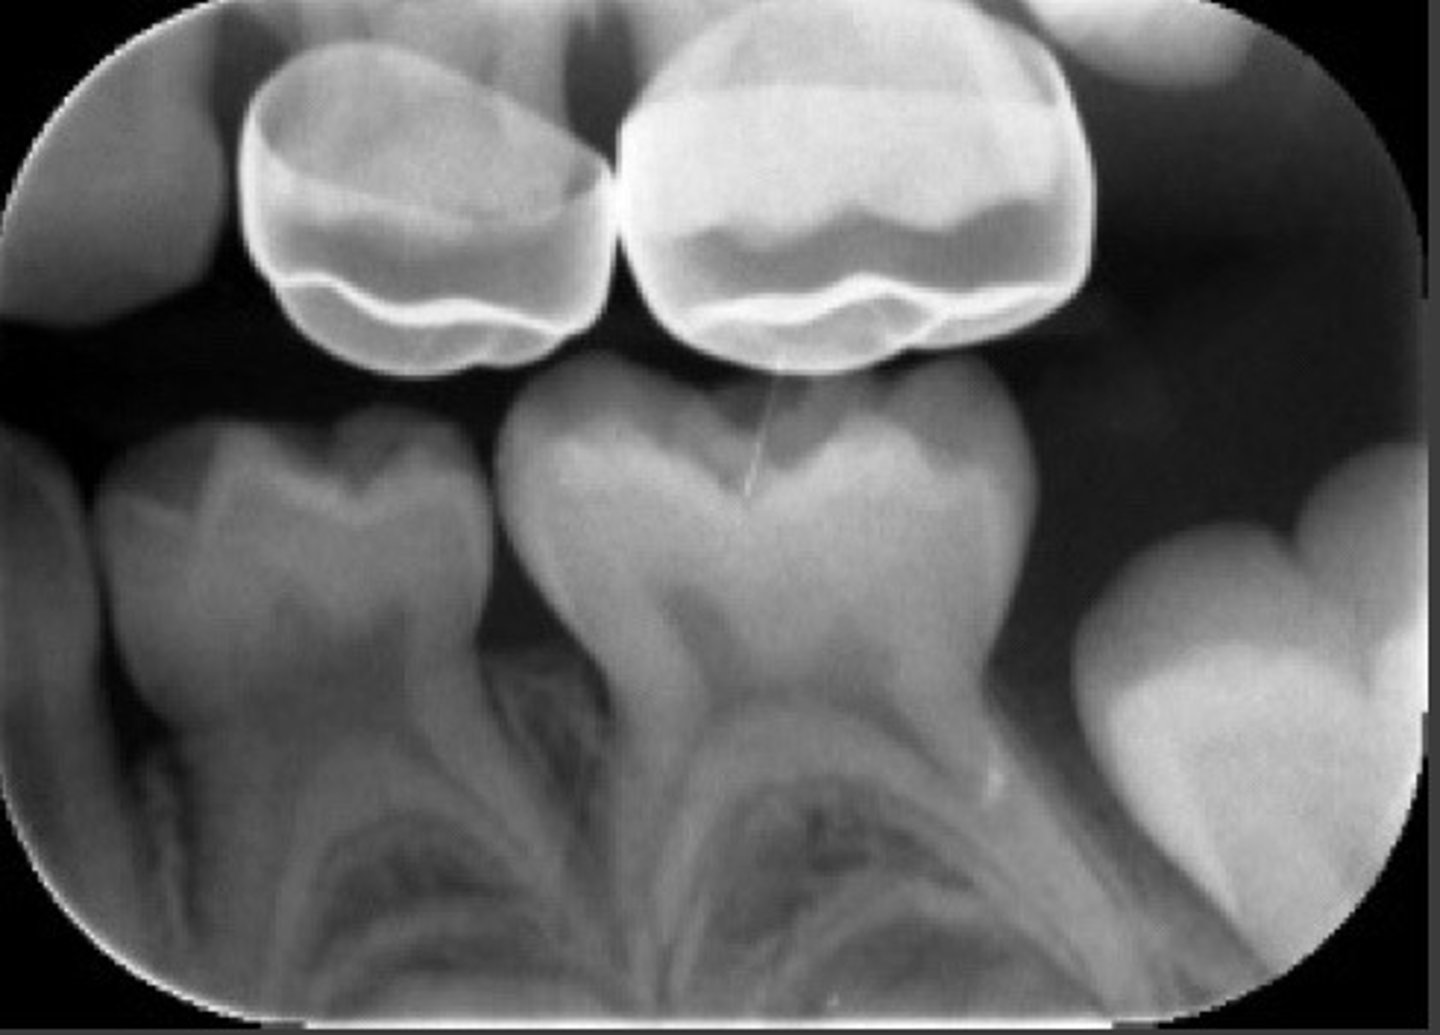

composite restorations radiographically